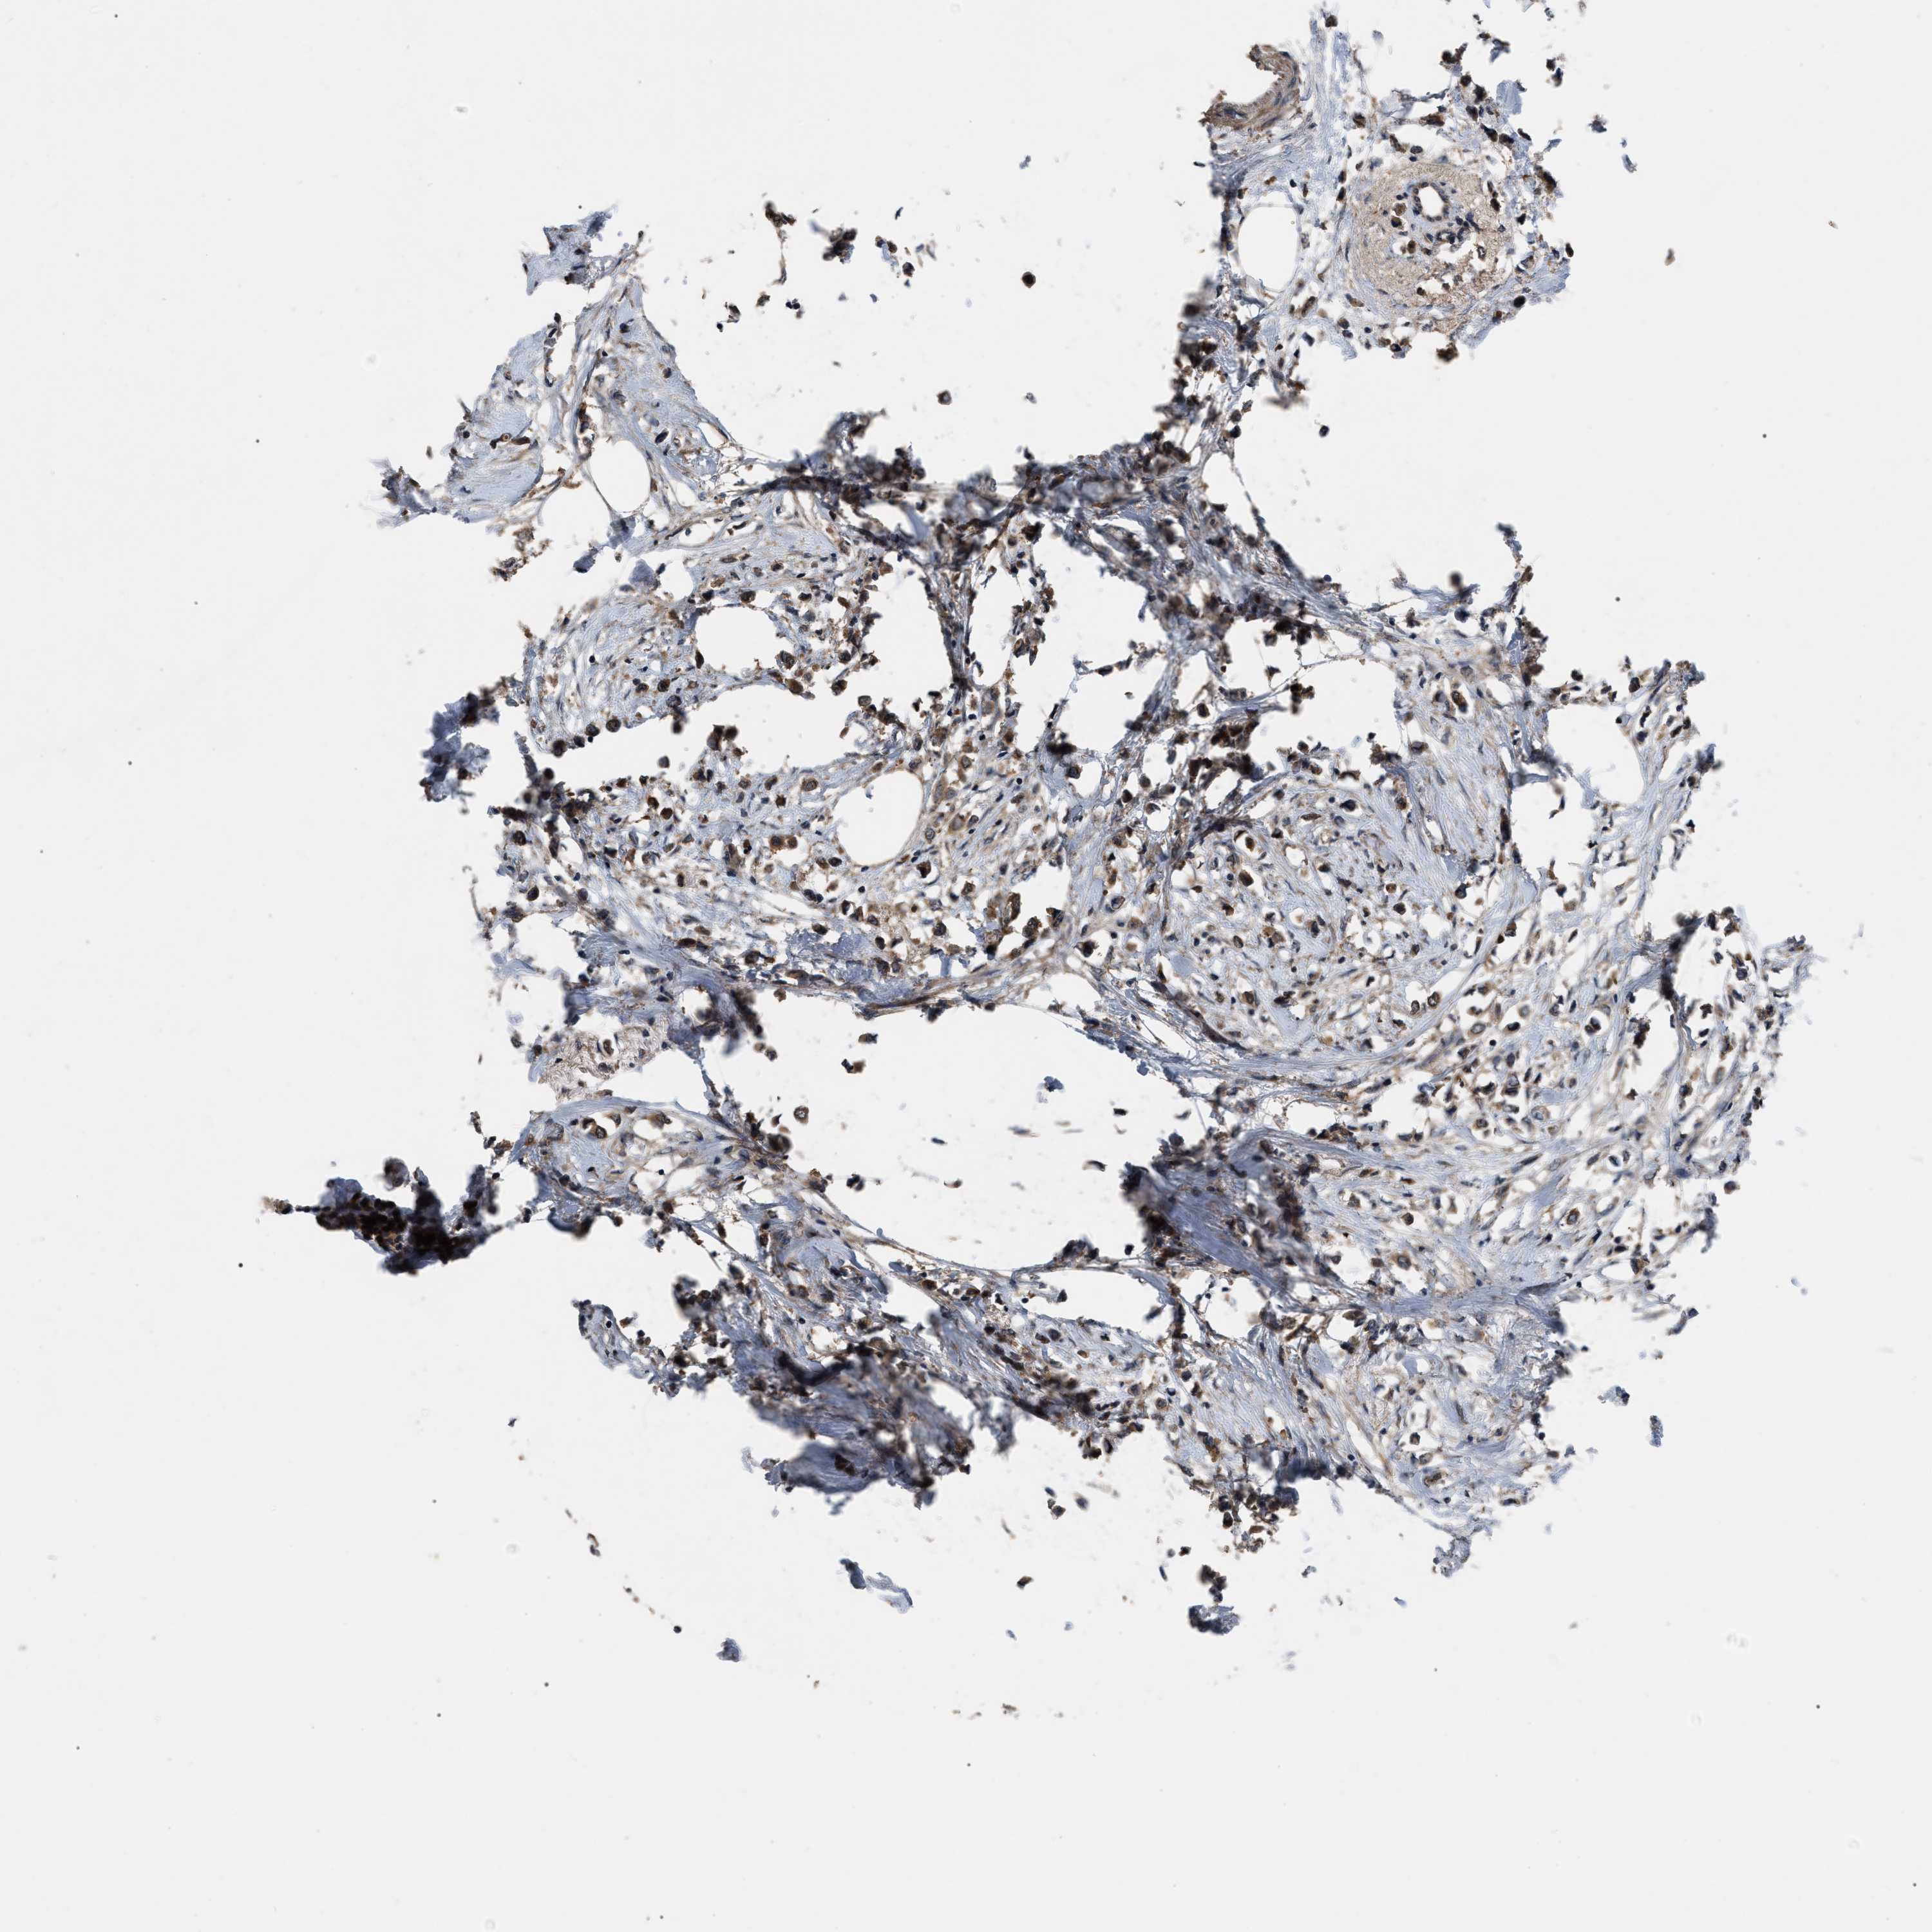

CANCER BREAST CANCER Show tissue menu

Breast cancer

Human cancer